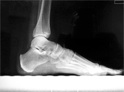

POSICION 2 : PIE L (LATERAL O PERFIL)

Paciente en decubito lateral, apoyando la cara lateral del pie sobre el cassete.El haz de rayos es dirigido verticalmente al centro del tarso.

CONSIDERACIONES MEDICAS Posicion 2 : PIE LATERAL

Enfoque complementario al frente de pie pero también importante en la apreciación de la patología talar y astragalina , no así el ante píe puesto que es mejor observado en el frente, , sin embargo es de uso común en la mesura de los arcos plantares ,

Los sesamoideos pueden ser observados en este enfoque en conjunción con un enfoque oblicuo , mucho de la patología plantar en lo que respecta a la fascia plantar y su inserción es mejor apreciada en este enfoque . Dr.Aramayo